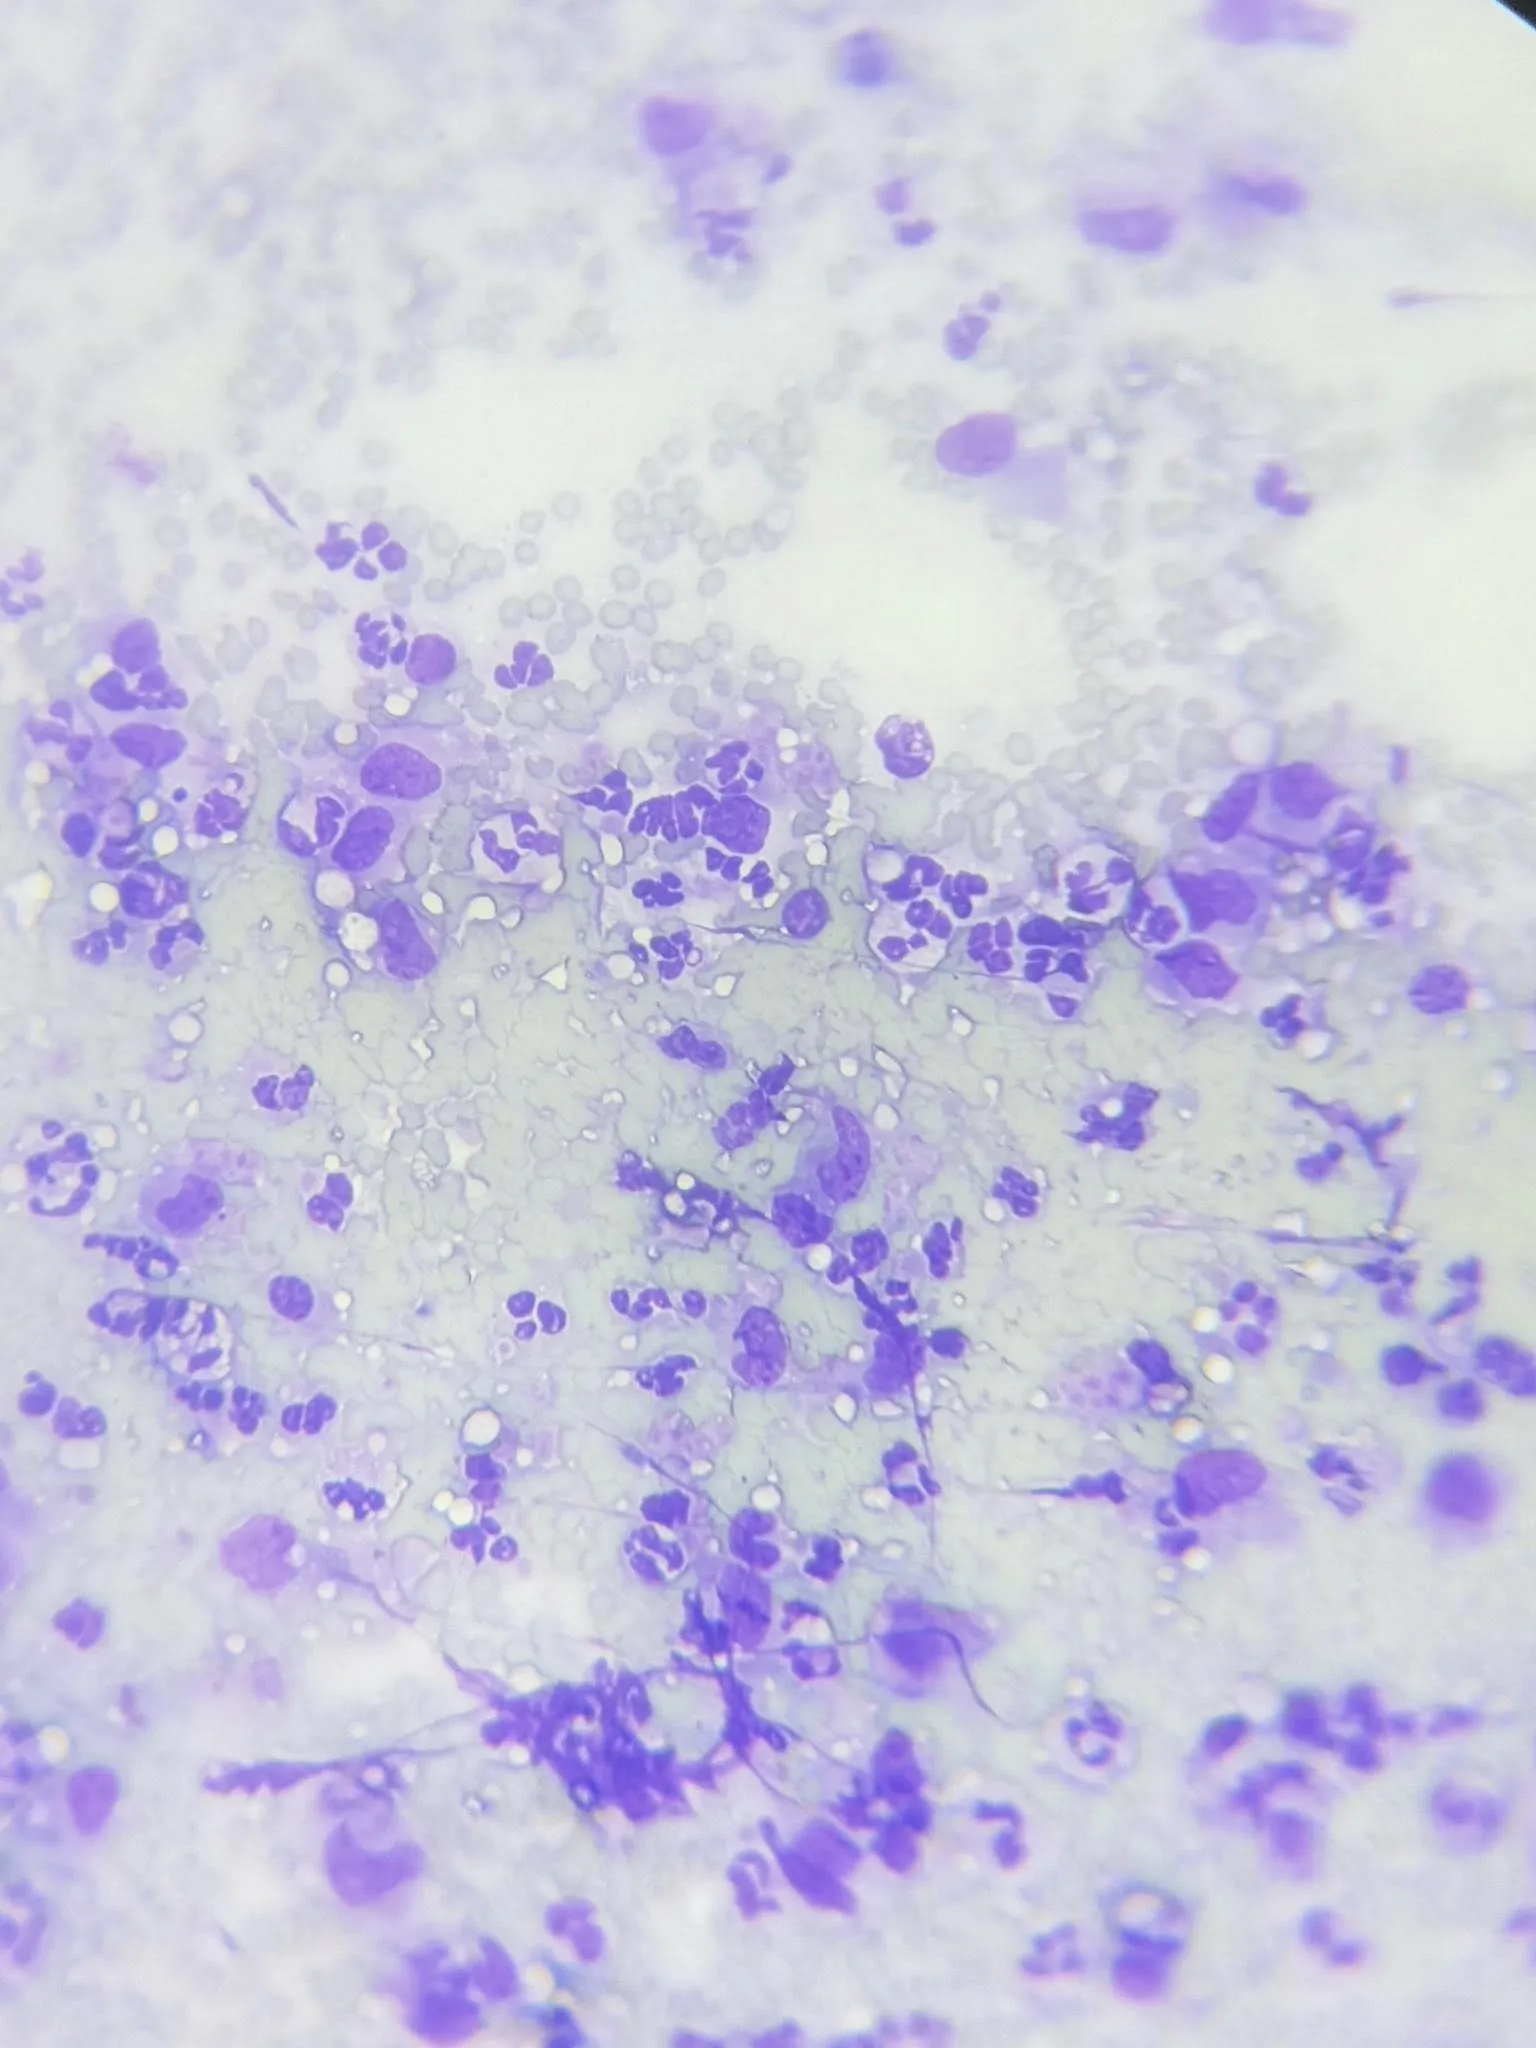

抽出的腹水呈黃色黏稠,血檢球蛋白很高——高度懷疑是傳染性腹膜炎(FIP)。

✔️ 細胞學分析顯示非惡性腫瘤 (為化膿性肉芽腫性炎症)

抽出的腹水呈黃色黏稠,血檢球蛋白很高——高度懷疑是傳染性腹膜炎(FIP)。

✔️ 細胞學分析顯示非惡性腫瘤 (為化膿性肉芽腫性炎症)